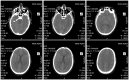

We describe the clinical features of five cases of Lujo hemorrhagic fever and summarize their clinical management, as well as providing additional epidemiologic detail regarding the 2008 outbreak. Illness typically began with the abrupt onset of fever, malaise, headache, and myalgias followed successively by sore throat, chest pain, gastrointestinal symptoms, rash, minor hemorrhage, subconjunctival injection, and neck and facial swelling over the first week of illness. No major hemorrhage was noted. Neurological signs were sometimes seen in the late stages. Shock and multi-organ system failure, often with evidence of disseminated intravascular coagulopathy, ensued in the second week, with death in four of the five cases. Distinctive treatment components of the one surviving patient included rapid commencement of the antiviral drug ribavirin and administration of HMG-CoA reductase inhibitors (statins), N-acetylcysteine, and recombinant factor VIIa.